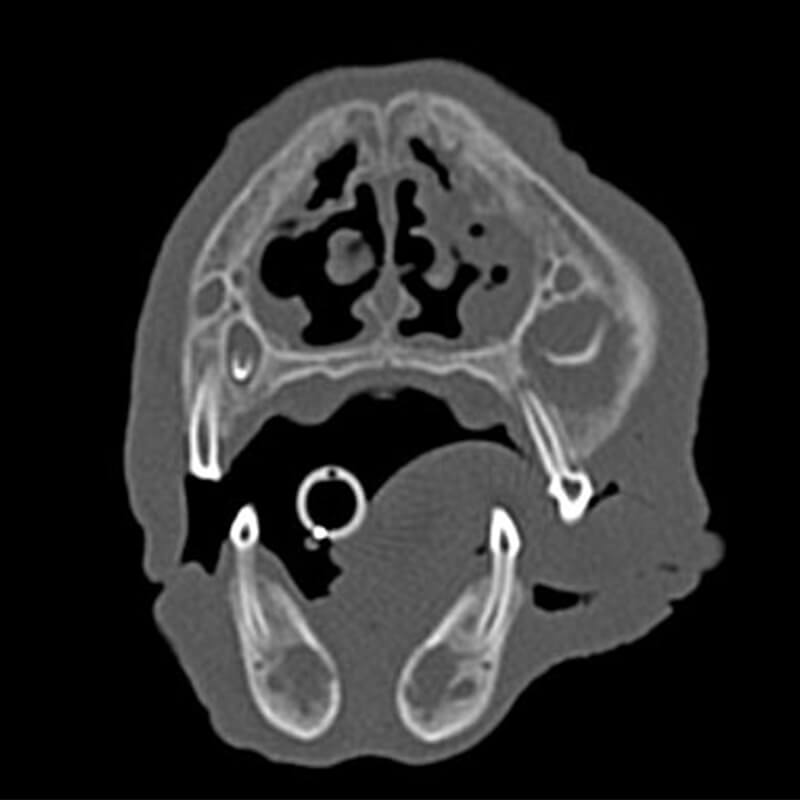

Labrador Retriever Bella, 9 Jahre

Sequenz nach intravenöser Kontrastmittelgabe

Den atlantokzipitalen und atlantoaxialen Übergang umgebend stellt sich eine zum Weichteilgewebe hypoattenuierende, in multiple Kavernen unterteilte Raumforderung dar. Die Dichte der einzelnen Kavernen beträgt ca. 11-13 HU (Dichte der benachbarten Muskulatur ca. 80 HU). Eine, von den übrigen Veränderungen scheinbar isolierte, hypoattenuierende Raumforderung ist ventral des M. longus capitis sichtbar. Sie misst ca. 3,8 × 2,5 × 4,1 cm (L x H x B). Sie führt zu einer hochgradigen Vorwölbung des Pharynxdaches, sodass der Nasopharynx vollständig verlegt wird. Das Os occipitale, das Os temporale, der Atlas (C1) und die cranialen Anteile des Axis (C2) inklusive des Dens axis zeigen hochgradige, scharf begrenzte Osteolysen. Die Veränderung dehnt sich rechtsseitig in die Fossa cranii caudales aus und führt zu einer geringen Verlagerung und Kompression des Vermis cerebelli. Ebenso werden der Hirnstamm und im weiteren Verlauf der Beginn des Rückenmarks innerhalb des Wirbelkanals von C1 und C2 komprimiert. Dabei findet die Kompression im Bereich Hirnstamm und Rückenmark vor allem von ventral und von den Seiten her statt. Nach Kontrastmittelgabe zeigt sich innerhalb des Wirbelkanals von C1 und C2 eine hochgradige, heterogene, schwammig erscheinende Anreicherung ventral und lateral. Die Anreicherung betrifft die Strukturen, welche zu einer Kompression und Verlagerung des Rückenmarks führen. Die großen hypoattenuierenden, kavernenartigen Veränderungen zeigen keine Kontrastmittelaufnahme.

CT Diagnose

- Weichteilneoplasie atlantokzipitaler und atlantoaxialer Übergang mit Destruktion des Knochens und Kompression von Kleinhirn, Hirnstamm und Rückenmark

Die Veränderung ist verdächtig für ein Myxosarkom. Differenzialdiagnostisch kann es sich um eine andere Weichteilneoplasie handeln, allerdings ist die geringe Dichte hochverdächtig für ein Myxosarkom. Der Tumor geht vermutlich von dem atlantokzipitalen und atlantoaxialen Gelenk aus, welche miteinander kommunizieren. Es daher davon auszugehen, das die beschriebenen Raumforderungen miteinander in Verbindung stehen und Ausdruck einer Neoplasie sind.